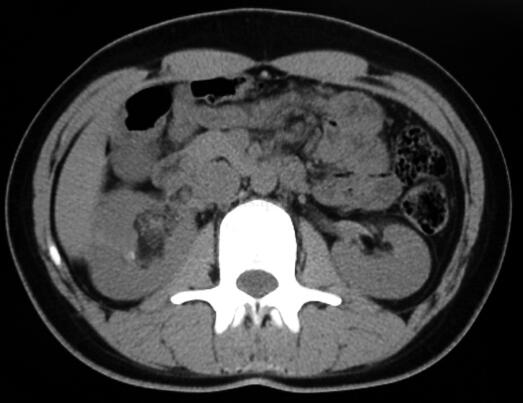

CT平扫:右肾盂旁可见一个不规则团块状混杂密度影,大小4.5cm×2.9cm×1.9cm,最低密度CT值为-40HU。增强扫描病变组织部分明显强化,最高CT值达97HU。增强后显示病变主要位于肾窦,并紧贴肾血管走行,一部分病变组织延伸至肾静脉内,一部分病灶压迫肾盂并与肾实质分界不清,右肾上、中盏受压变形(图1~图4为该肿瘤的部分CT扫描图像)。

图1 CT平扫右肾盂旁可见一个混杂密度病灶,最低密度CT值为-40HU